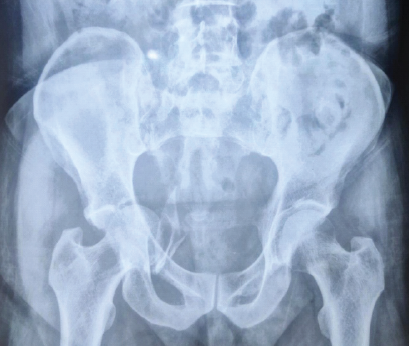

A Large-diameter Corona Mortis Artery Encountered During Surgery for Acetabular Fracture: A Case Report and Review of Anatomical Significance

Anteshwar Birajdar , Mukesh Phalak , Tushar Chaudhari , Damarla Meghana

………………………………p.133-136